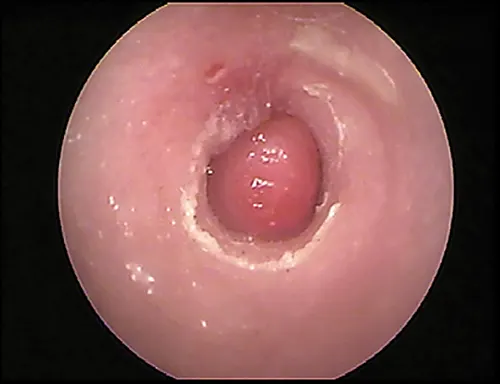

Damage to the tympanic membrane caused by trauma (eg, chewing activity of ear mites, previously ruptured eardrum that has healed) or chronic infection disturbs this epithelial migration process. When epithelial migration is slowed, as with age or from disease, debris, cerumen, and hairs accumulate on the eardrum. A ceruminolith may develop on the eardrum on the external ear canal side (Figure 14). These plugs may also consist of dried mucus or medication that has hardened in the horizontal canal.

Globoid brown-to-black mass occluding internal ear canal.

FIGURE 14

Wax plug (ceruminolith) on the eardrum

Wax plug in an ear. Accumulations of wax (cerumenolith) commonly  show up at the eardrum when the eardrum epithelial surface has been previously compromised.  Dried oily medication and inspissated mucus from the bulla can look similar.

Cerumen accumulation against the eardrum, in addition to stenosis and hyperplasia, can impede conduction of sound waves and result in temporary hearing loss. Ceruminoliths require mechanic removal, preferably with endoscopic grasping forceps through a video otoscope with the patient anesthetized. If the eardrum is not intact, exudates such as mucus and pus can leak into the horizontal canal and inspissate at the eardrum. This condition can look like a ceruminolith. The mucoid secretions dissolve in water and can be removed with a water or saline flush of the horizontal canal.